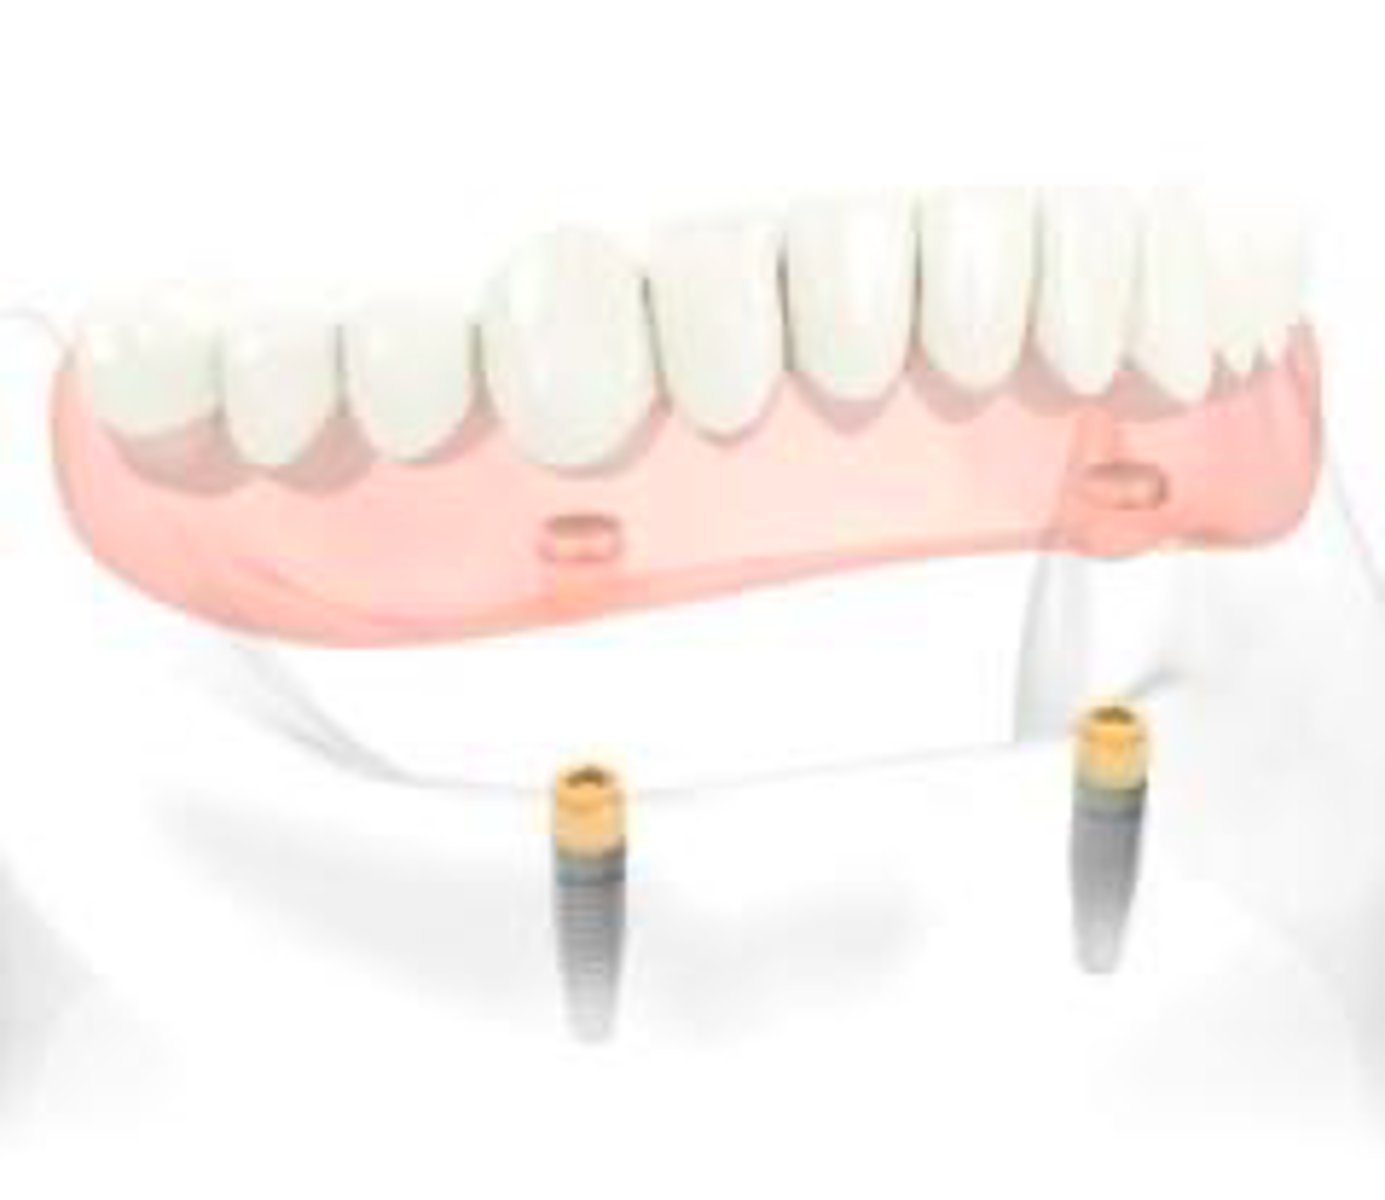

Implant-retained/ tissue-supported

Describe the retention and support for this denture

Implant-retained/ implant- supported

Implant-assisted removable complete denture

What are these images showing?